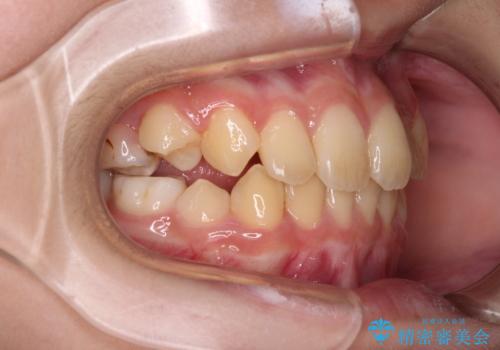

- 前歯の叢生を気にして来院された、小学校3年生女児の患者様です。

身長がやや低く、乳歯から永久歯への交換が少し遅い印象があったので、ワイヤー装置による1期矯正治療ではなく、乳歯も積極的に動かすことのできるインビザライン・ファーストにて治療を行うこととしました。

上顎前歯に過剰歯があったため、まずはその歯を抜歯し、傷が治癒したタイミングでインビザラインを発注することとしました。